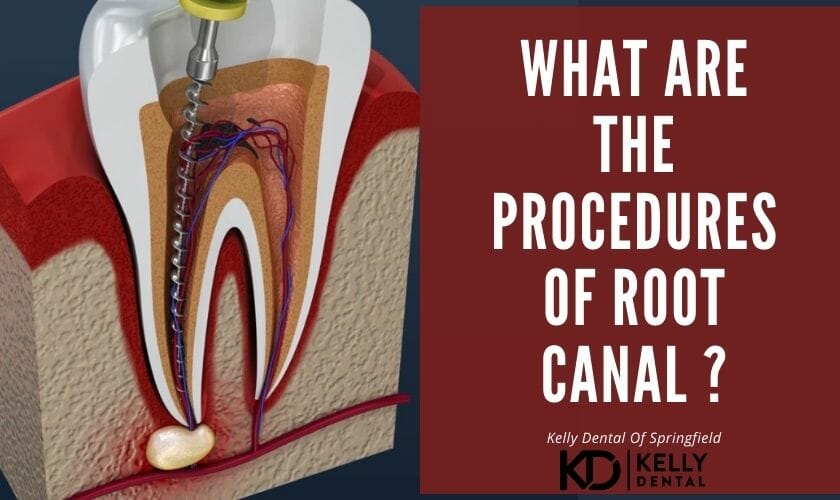

What Are The Procedures Of Root Canal ?

A root canal is a process to fix and save a tooth that has been damaged or is infected instead of removing it. As the canals inside a tooth’s root are cleaned, this is called the “root canal.”

How is a root canal done?

Getting rid of the pulp

A small hole can be made on your tooth when your tooth is numb. They’ll use particular tools called files to gently remove the infected or damaged pulp. They’ll be cautious to clean out all of your tooth’s pathways (canals) and make sure they’re all clean.